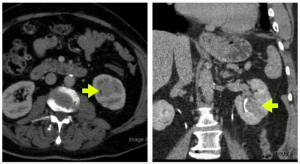

Then in 2021, the patient re-engages with us, at 79-years-old, with an ultrasound and CT scan, where we note a 3.5x5cm lesion in the left lower pole.

We did a salvage radical nephrectomy, results below:

Patient was pT3a (renal vein invasion), with Post op serum Cr.1.6

Patient is doing well and has not developed metastasis (Mar 2022).